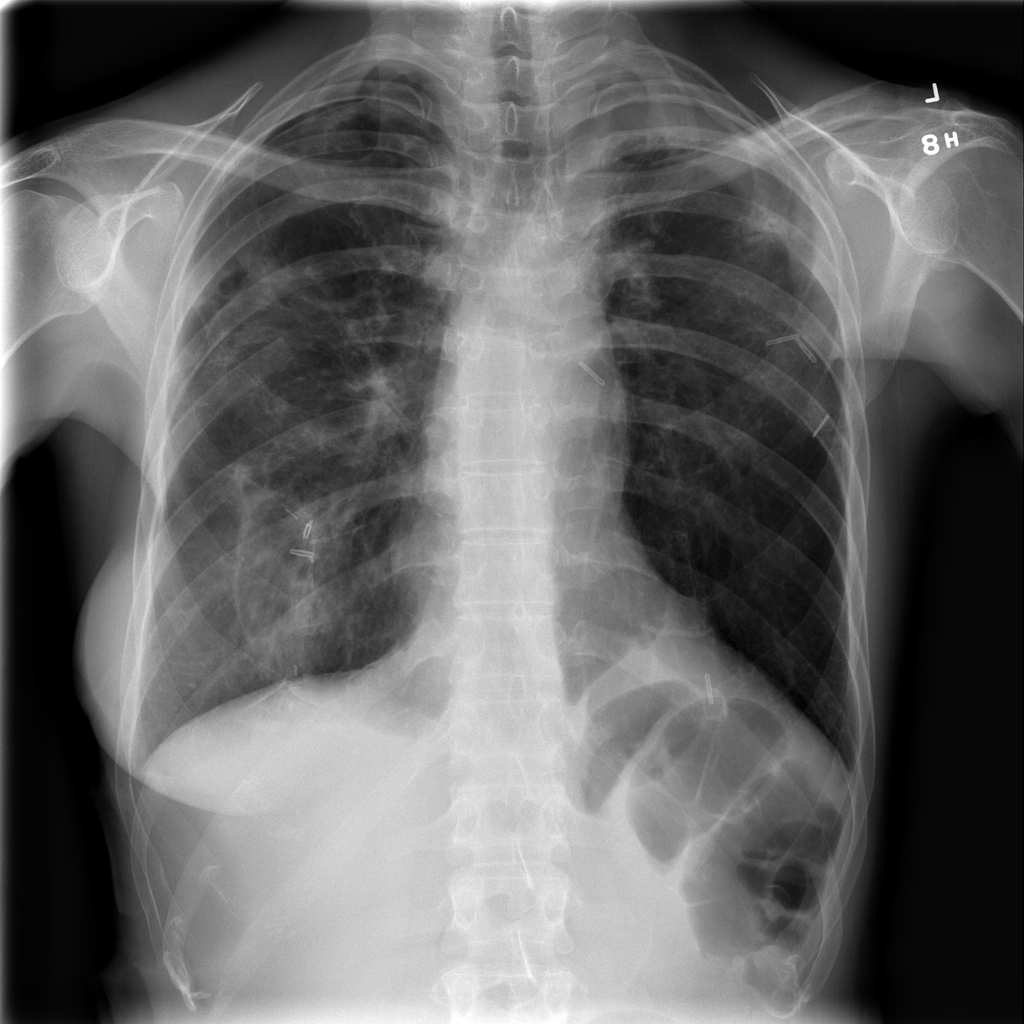

PAT-C77C · IMG-003Fibrosis

PAT-C77C · IMG-003

PA